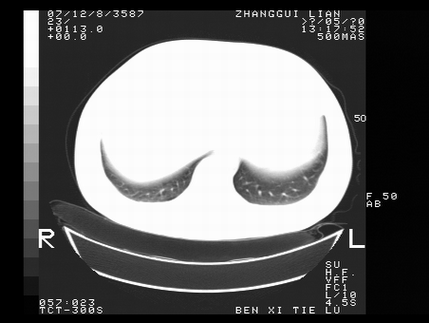

标题: CT10818:男,73,TB病史,现病史肺炎及直肠CANCER术后 [打印本页]

标题: CT10818:男,73,TB病史,现病史肺炎及直肠CANCER术后

这个请版主删除掉,这个病例我发过的,发重了,此人病史是,f,46y,胸疼,无其他原因就诊

左侧中央型肺癌伴阻塞性肺炎\\不张,左侧前上纵隔亦增宽,建议上传纵隔窗除外淋巴结转移.

考虑:左侧中央型肺癌伴阻塞性肺炎,纵隔淋巴结转移。

1)考虑为:左侧中央型肺癌伴阻塞性肺炎,纵隔淋巴结转移。2)双侧少量胸腔积液。3)心包积液。

左侧中央型肺癌伴阻塞性肺炎,纵隔淋巴结转移。

考虑左侧中央型肺癌伴阻塞性肺炎,纵隔淋巴结转移。